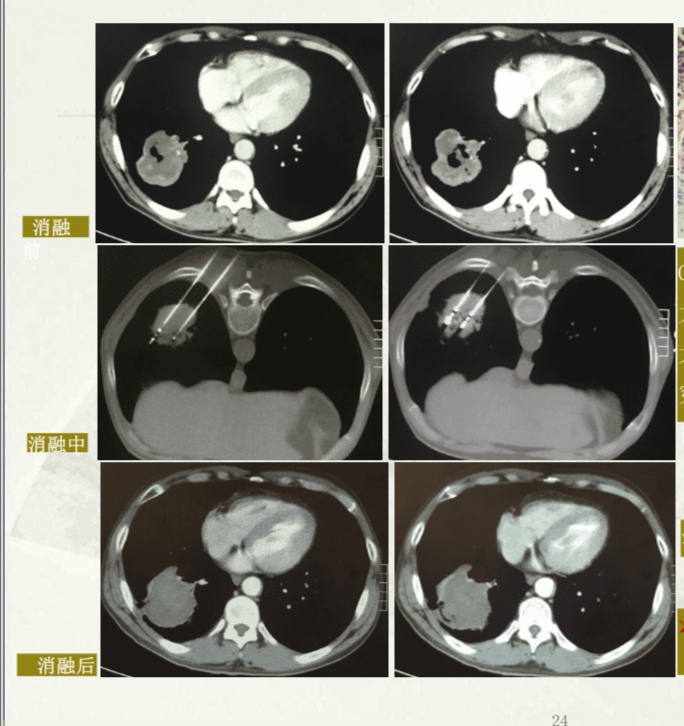

肿瘤射频消融术是肿瘤消融术治疗当中最常用的一种方法,其主要的原理是利用电极头部发出的中高射频射波,使细胞内的温度超过60度,而达到破坏肿瘤细胞的目的,同时也可以使肿瘤周围的血管组织凝固形成一个反应带。而射频消融主要用于像肝,肺,肾,肾上腺骨转移癌等一些实体肿瘤,并且可以取得良好的治疗的效果,而且对于早期的肝癌和一期的非小细胞肺癌患者有较好的治疗效果,同时也是中晚期肿瘤姑息治疗的重要治疗手段。所以建议患有恶性肿瘤的患者,要听从专业医生的意见,选择规范的治疗的方案。